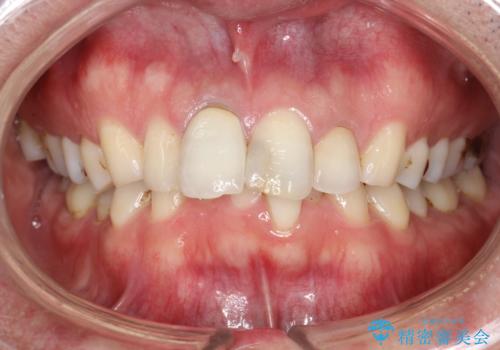

- 約3年ほど歯科医院での定期健診やクリーニングを受けてないとのことでした。全体的に歯石・着色などが付着していていたためPMTC60分コースを行いました。

分厚く歯石や着色が付着していると、汚れなのか虫歯なのかの判別がしづらい場合があります。しばらく定期健診やクリーニングを行っていない場合は、まずはしっかりと汚れを除去し、本来のご自身の歯の状態にすることで、より精密なお口の状態の診断が行えます。

PMTCによって、CRと、ご自身の歯の境目の着色などがしっかりと落とせて目立たなくなる場合と、PMTCによってしっかりとクリーニングを行うと、CR自体が古く劣化・変色などしていて目立ってくる場合があります。気になる際は詰め替えを行います。